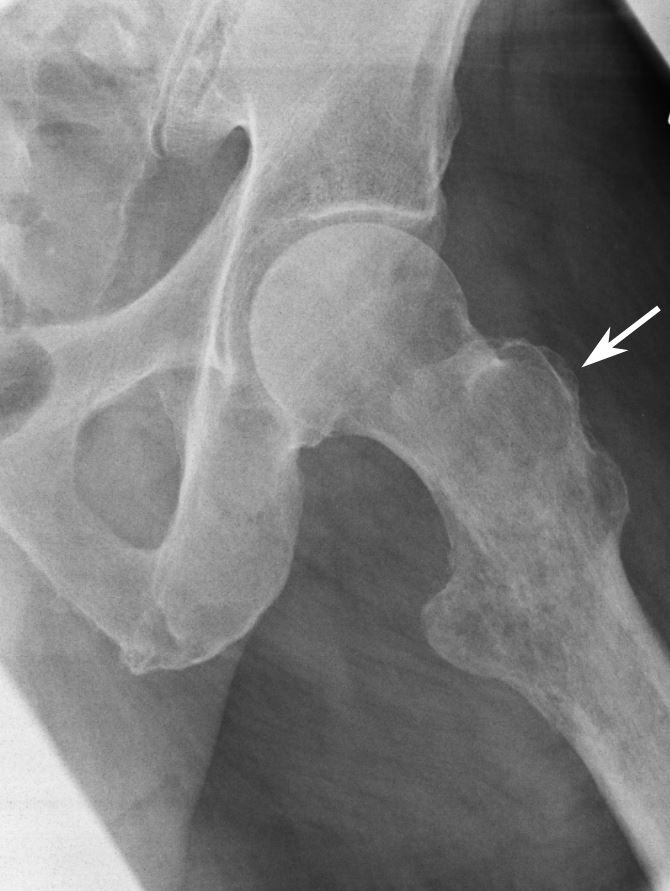

X-ray of tumor

X-ray shows a tumor in the upper part of the femur (thighbone).

Reproduced from Biermann JS, ed: Orthopaedic Knowledge Update: Musculoskeletal Tumors 3. Rosemont, IL, American Acad of Orthopaedic Surgeons, 2014, p 206.